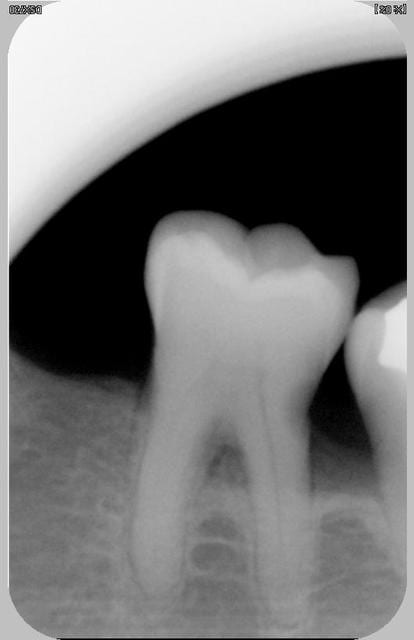

pour la radio 2 il y a une carie proximale mésiale au niveau radiculaire

pas sûr pour la carie mais sinon je pense qu'il s'agit d'un syndrôme septum faut leur apprendre à faire soins locaux avec brossettes

La deuxième,elle a tout pour plaire quand même

le probleme de la 2eme pourrait etre l'egression par manque d'antagoniste par exemple

consequence rupture du point de contact et précarie mesiale associé à une prélesion interadiculaire et à une hypersensibilité radiculairedentinaire mesiale liee à la rupture du point de contact mesial

a mon avis il y a carie .point!,qui agrave surement encore le problème paro,ou bien provoquée par le problème paro,mais le résultat final est là,pas si obscur comme diagnostic!

L’égression d’une dent se fait normalement avec son parodonte (c’est le principe même de l’orthodontie), une simple égression ne peut donc pas expliquer la perte osseuse de ce cas n°2.

perte osseuse ou pas il y a bien une carie ...

et c'est ce qui motive la consultation

la carie sur la 2ieme photo atteind la moitier dentinaire, ce n'est pas une lesion débutante, donc il n'y a pas de reminéralisation possible